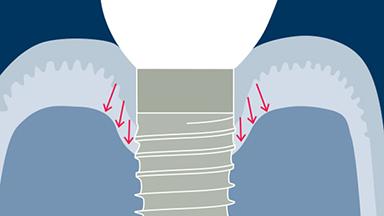

- understand how microbial biofilms form on implants and lead to soft tissue inflammation

- identify the effects of inflammation on the peri-implant soft tissues